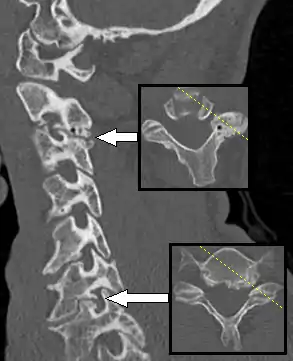

Multiplanar reconstruction and projections

Multiplanar reconstruction (MPR) is the process of converting data from one anatomical plane (usually transverse) to other planes. It can be used for thin slices as well as projections. Multiplanar reconstruction is possible as present CT scanners provide almost isotropic resolution.[105]

MPR is used almost in every scan. The spine is frequently examined with it.[106] An image of the spine in axial plane can only show one vertebral bone at a time and cannot show its relation with other vertebral bones. By reformatting the data in other planes, visualization of the relative position can be achieved in sagittal and coronal plane.[107]